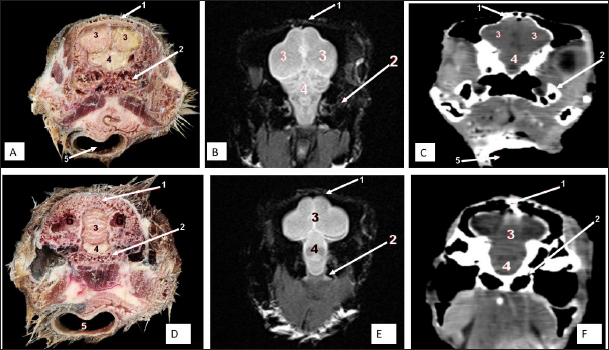

Fig. 6. Rostral-caudal cross sections of the adult ostrich head—level 1. Rostral views of A) photograph of an anatomical cross section, B) MRI and C) computed tomography images (rostral view) showing: a- Rostral nasal concha, b- Dorsal nasal recess, c- Ventral nasal recess, d- Nasal septum. Caudal views of D) an anatomical section photograph, E) MRI and F) computed tomography images showing: 1- Os nasale, 2- Os maxillare, 3- Vomer, 4- Nasal septum, 5- Infra orbital sinus, 6- Frontal sinus, 7- Mandible, 8- Tongue, a- Middle nasal concha (bulla), b- Middle nasal concha, c- Middle nasal meatus, d- Ventral nasal meatus, and e- Rostral nasal concha mucosal fold.

Fig. 7. Rostral-caudal cross sections of the adult ostrich head—level 2. Rostral views of A) photograph of an anatomical cross section, B) MRI and C) computed tomography images showing: 1- Processus.frontalis, 2- Os maxillare, 3- Vomer 4- beginning of the orbit, 5- Infra orbital sinus, a- Middle nasal concha, b- Dorsal nasal meatus, c- Ventral nasal meatus, d- Nasal septum. Caudal views of D) anatomical cross section, E) MRI, and F) computed tomography images showing: 1- Processus. frontalis, 2- Frontal sinus (separated by the median septum), 3- Lateral nasal process, 4- Processus.jugalis, 5- Nasal septum (two ridges separated by an empty groove), 6- Caudal nasal concha, 7- Ventral nasal meatus, 8- Infra orbital sinus, 9- Palate, 10- Oropharynx, 11- Laryngeal cavity, and 12- Eye ball.

The nasal conchae exhibited in the MRI images as bright (high or hyperintense signal intensity) to gray (low or hypointense signal intensity) structures that could be divided into three parts: rostral, middle, and caudal conchae, which correlated to the morphological examinations. In contrast, the nasal conchae could not be recognized clearly on CT images compared to those obtained after MRI (Figs. 25 B and C). The paranasal sinuses with other structures could be identified using both CT and MRI. The nasal septum and paranasal sinuses revealed a white bone border (high signal intensity), soft tissue was grey (low-to-intermediate signal intensity), and they contained black gas, so both the CT and MRI scans showed little signal intensity (Figs. 15B and C and 79B, C, E, F).